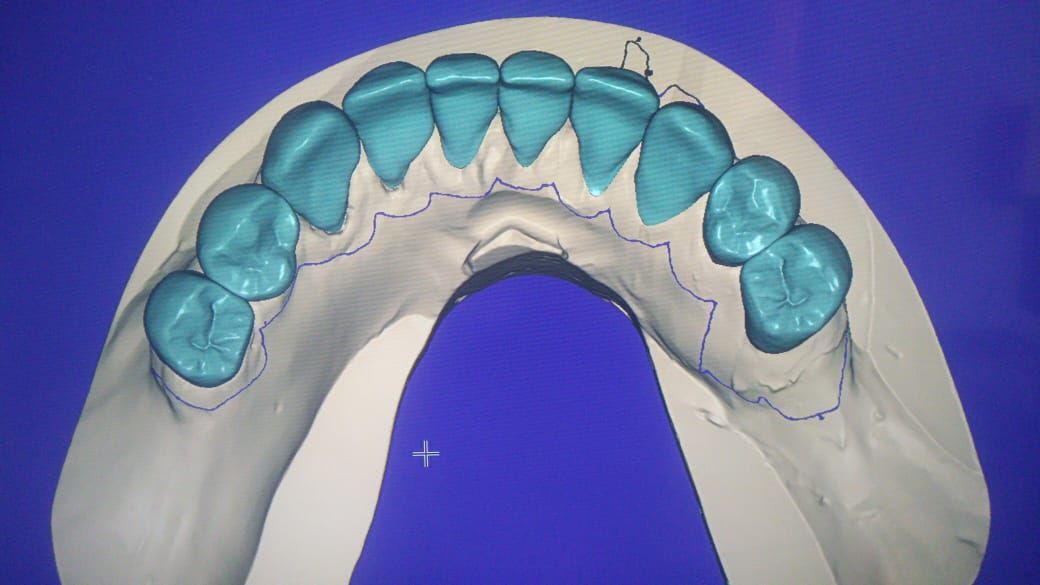

Contamos con tecnología de punta que nos facilitara el diagnostico y tratamiento de tu problema dental lo cual hará mas predecible el éxito a largo plazo.

Especialista en Implantología Oral quirúrgica y protesica, cédula de especialidad: 12411844

La especialidad en Implantología Oral se enfoca en sustituir órganos dentarios perdidos por implantes dentales mediante una fase quirúrgica y una fase protesica y de esta manera devolver la función, estetica y confort dental del paciente.